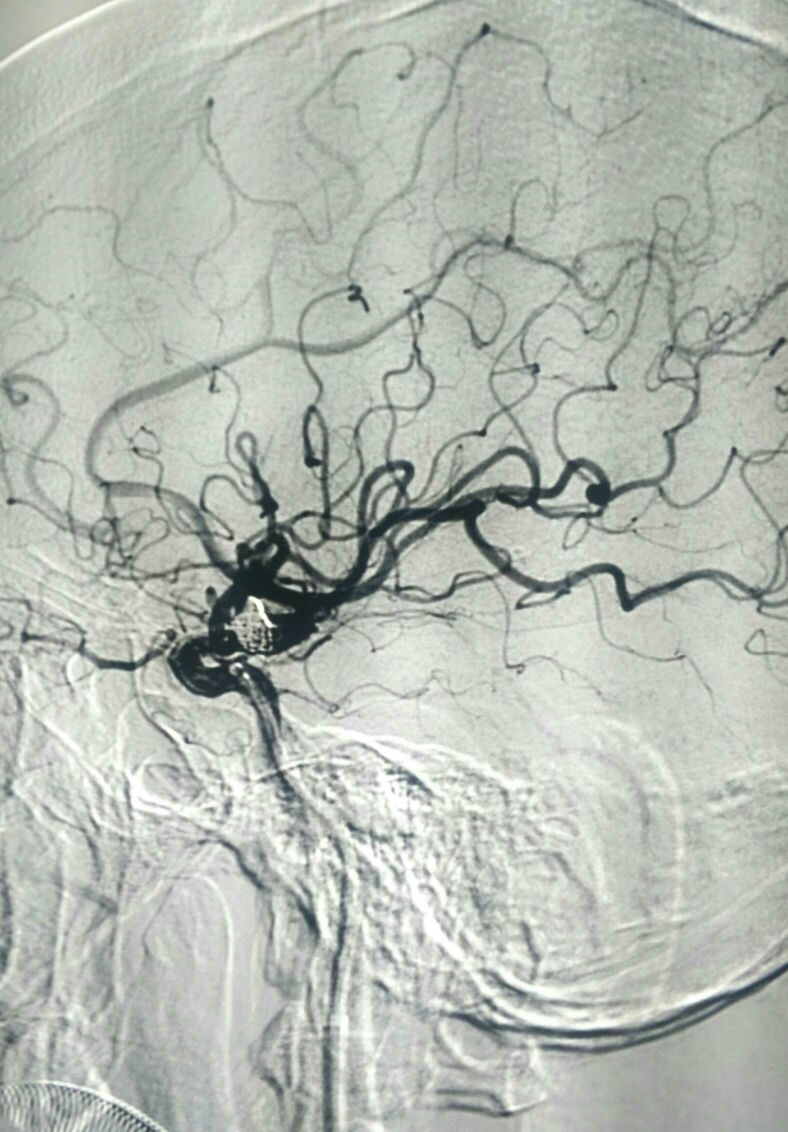

DSA左侧ICA“血泡”样动脉瘤

动脉瘤大小5.5*8mm

栓塞工作角度33/-28影像满意

正位像栓塞影像满意

侧位像满意